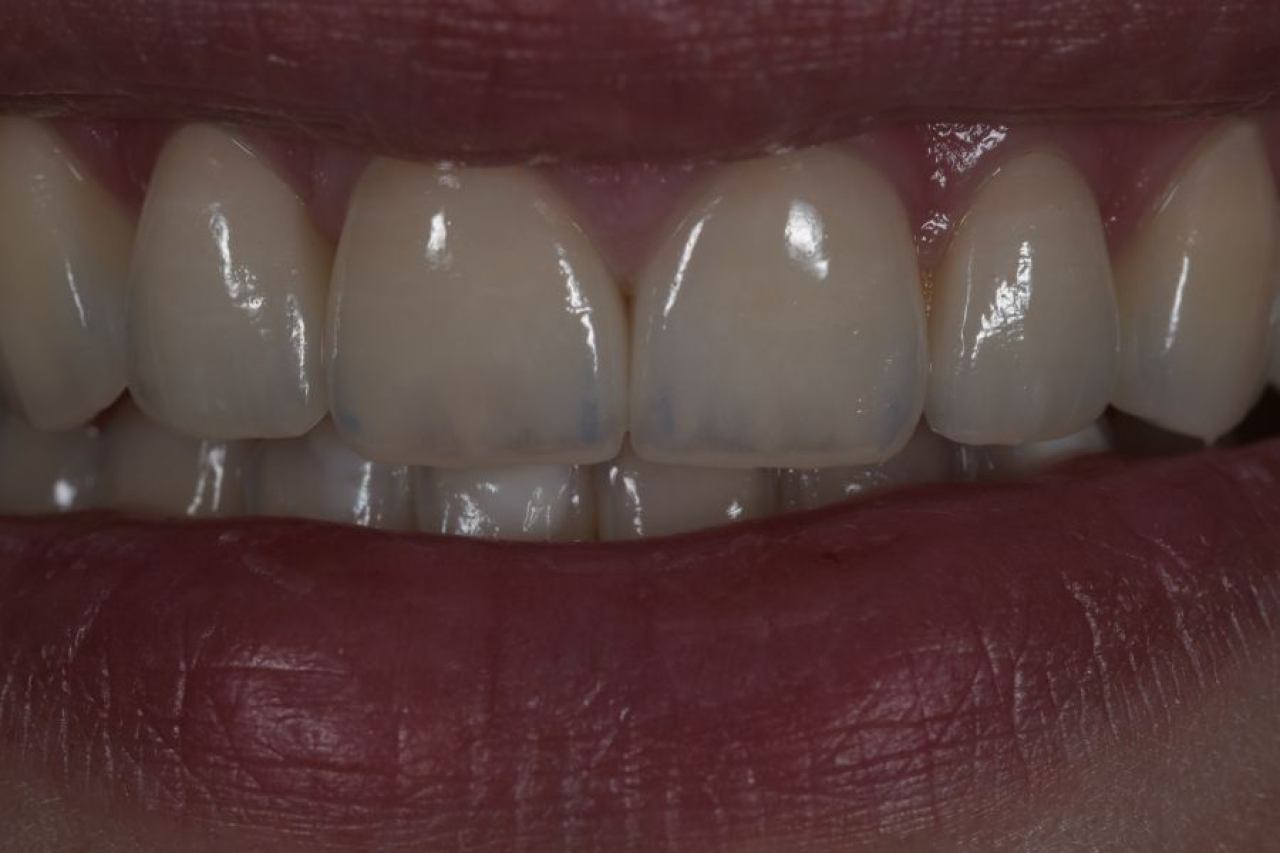

Estetska dentalna medicina

Izbjeljivanje zubi i zubne ljuskice zaštitni su znak Hollywoodskog osmijeha. Izbjeljivanje nije štetno za zube i ne oštećuje caklinu.

Ukoliko niste zadovoljni svojim osmijehom tu je DSD ili Digital Smile Design kojim u okvirima naših mogućnosti ispunjavamo vaše želje „Hollywood smile" ljuskicama, minimalno invanzivnim preparacijama zuba.

Marković Dental Clinic uvijek na prvom mjestu ima zdravlje zubi i zadovoljstvo svakog pacijenta. Koristimo najmoderniji software gdje je pacijentu moguće virtualno prikazati nove zube te kasnije kreirati novi osmijeh protetskim radom, ljuskicama, krunicama ili mostovima.